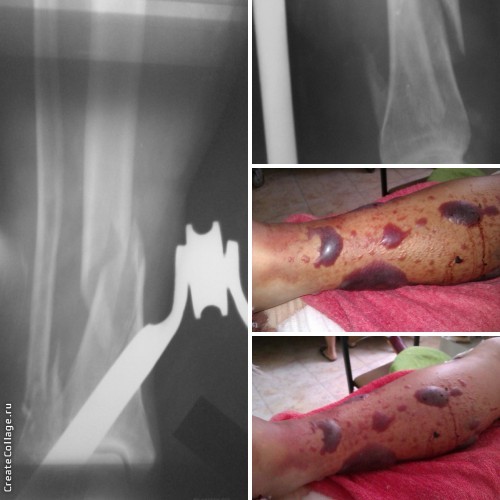

Длительное время все такие пузыри мы вскрывали и лечили под повязками. Но ряд коллег начали лечить данные состояния просто ожиданием без всяких подрезаний, выпусканий...и очень довольны результатами. В приложении фото пациентки 56 лет с переломом обеих костей голени в нижней трети. На "своих ногах" пришла в больницу и в результате картина, представленная на фото (на 2 сутки после перелома).

Коллега правильно сказал, что это патогномоничный признак повышения внутритканевого давления, которое складывается из трех компонентов: отека в фасциальных футлярах травмированных мышц, гематом и сдавливающих наружных повязок. В представленном случае имеет место банальный винтообразный перелом.Поэтому главный фактор появления фликтен - это препятствие расширению объема внешними повязками.Фликтены лучше вскрывать в стерильных условиях проколом по нижнему полюсу и рыхло обложить повязками с раствором бетадина. После прекращения отделяемого - очистить от остатков некротизированного эпидермиса. Естественно, все это делать на фоне малотравматичной, точной репозиции и стабильной фиксации. В таких условиях срок жизни таких ран не более недели.

Теперь по поводу фликтен, здесь главная задача не допустить вторичной инфекции. Огромные можно вскрыть и покрыть стерильной повязкой. Имеются готовые повязки в составе растительное масло и ксереформ. В отличие от других повязок масло покрывают поверхность и не прилипает.

В вашем случае скелетное вытяжение, сохраняется укорочение, можно добавить груз и сделать снимки. После спадения отека можно фиксировать интрамедуллярным гвоздем, потому что нельзя делать разрезы через зоны эпидермальных пузырей.